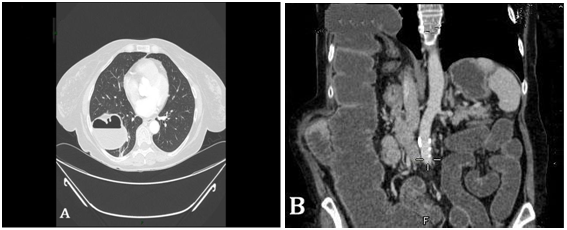

Iatrogenic diaphragmatic hernia is a rare complication and there are few cases in the literature.1 We report a case of a patient of 63 years with medical history of epilepsy, toxoplasmosis and necrotic and ulceratedhydatidcystwithseveregranulomatousforeignbodyreactionneeds formal right hepatectomy. She visited the emergency department of our hospital referring abdominal pain of 48 hours of evolution associated with constipation, nausea and vomiting. On examination, distended abdomen, painful on palpation, no defense and no abdominal peritonitis. Analytically objective leukocytosis with left shift. Presents a TC with intravenous contrast thoraco abdomino pelvic reporting of intestinal obstruction in relation to colon herniation through defect in right diaphragm (Figure 1). Naso gastric tube tone with plenty of intestinal contents, fluid therapy and broad spectrum antibiotics. The patient was operated emergency through the subcostal incision prior right aiming serous fluid turbid in moderation, firm adhesions in bed after surgery and diaphragmatic hernia hole about 4 cm through which laboriously reduces the hernia sac containing colon transverse dilated, and retrieving color peristalsis. Right diaphragmatic hernia repair is performed. She presented a good clinical response, initiating oral tolerance and intestinal transit recovering the 3rd day. The chest x-ray postoperative objectives the resolution of the right diaphragmatic defect (Figure 2). With standardization of analytical parameters and subcostal wound with good evolution is discharged to the 5th postoperative day.

Figure 1 Thoracoabdominal CT with intravenous contrast: 1A coronal cut, 1B sagittal section. Intestinal obstruction in relation to the transverse colon herniation through defect in right diaphragm.